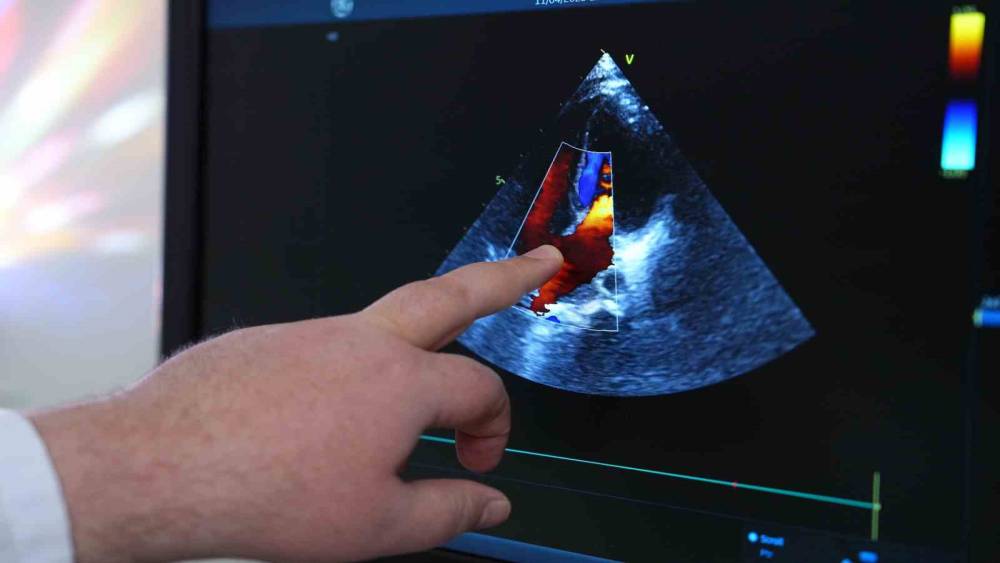

Çocuk Kardiyolojisi Uzmanı Prof. Dr. Cenap Zeybek, çocuklarda hipertansiyonun sinsi ilerlediğini ve çoğu zaman geç fark edildiğini ifade ederek, çocukların tansiyonlarının düzenli ölçülmemesinin, bu "sessiz düşmanın" belirlenmesini geciktirdiğini belirtiyor.

"Çocukların dünyasında gözden kaçan hipertansiyon, sinsi bir düşman. Çoğu zaman belirti vermeden ilerleyen ve bu nedenle çok geç fark edilen bu sağlık sorunu, küçük kalpler için büyük risk taşıyor. Türkiye’de maalesef çocukların tansiyon ölçümleri yeterince yapılmıyor" açıklaması yapan MedipolMega Üniversite Hastanesi Çocuk Kardiyolojisi Uzmanı Prof. Dr. Cenap Zeybek, özellikle kardiyolojiye yolu düşmemiş evlatlarda yüksek tansiyonun belirlenmesinin geciktiğini aktarıyor. Zira, yetişkinlerle kıyaslandığında hem nedenleri hem de tedavi yolları farklılık gösteren çocukluk çağı hipertansiyonunun mutlaka ciddiye alınması gerektiğini ifade eden Prof. Dr. Zeybek, konunun önemine dikkat çekiyor.